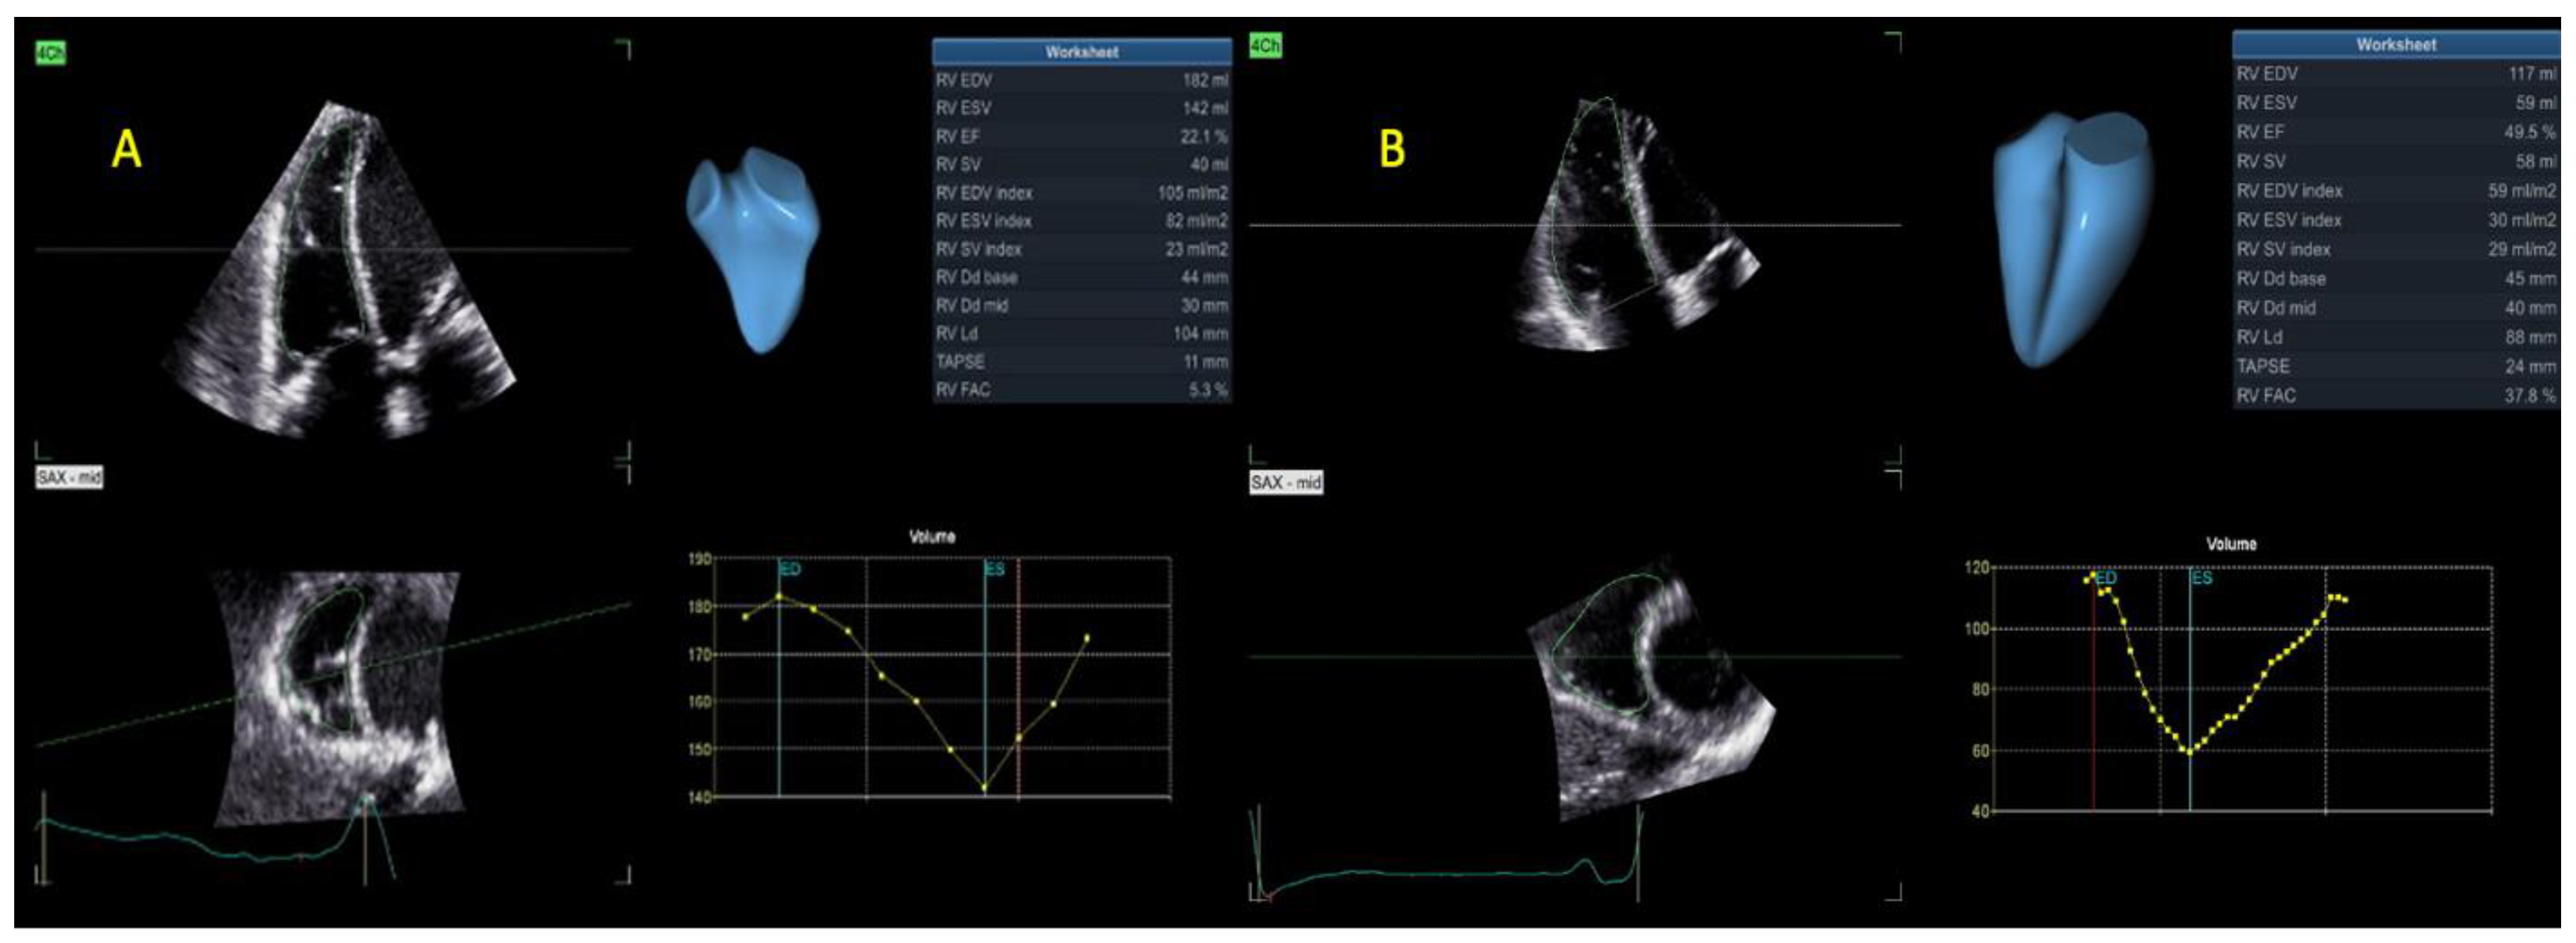

| 3D RVEDV (mL) | 93 ± 47 | 127 ± 59 | 0.01 |

| 3D RVEDV index (mL/m2) | 49 ± 25 | 67 ± 29 | 0.01 |

| 3D RVESV (mL) | 55 ± 35 | 80 ± 44 | 0.01 |

| 3D RVESV index (mL/m2) | 30 ± 19 | 43 ± 21 | 0.01 |

| 3D RVSV (mL) | 38 ± 16 | 47 ± 19 | 0.039 |

| 3D RVSV index (mL/m2) | 20 ± 8 | 25 ± 10 | 0.058 |

| 3D RVEF (%) | 44 ± 10 | 38 ± 8 | 0.03 |